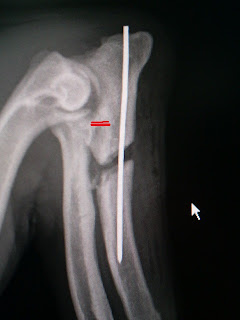

INCONGRUENZA ARTICOLARE

E’caratterizzata da uno scalino (due linee rosse nella rx )determinato da una eccessiva lunghezza del radio rispetto all’ulna o viceversa .

Bisogna porre molta attenzione nella interpretazione delle immagini radiografiche perche’ spesso e’ soggetto a false positivita’.Fondamentale e’ l’esame clinico del gomito che in caso di incongurenza presenta delle limitazione nella flessione del gomito con avvolte dolore . Nella deambulazione spesso e’ presente una zoppia moderata che si accentua con il movimento La terapia e’ chirurgica con una osteotomia prossimale dell’ulna( Dynamic Ulnar Osteotomy DUO)